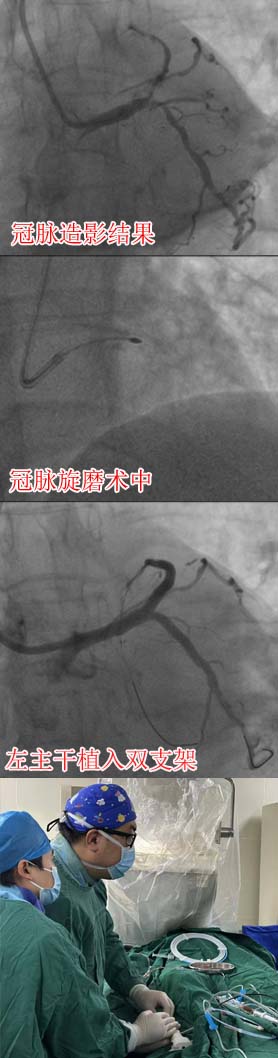

67岁的史女士因突发胸闷、胸痛入院,被诊断为急性前壁心肌梗死伴心力衰竭。入院后冠脉造影检查提示左主干分叉病变,累及前降支、回旋支,其中前降支血管近段存在弥漫性重度钙化,最狭窄的地方堵了99%,病情十分复杂危险,情况不容乐观。

在中国医学科学院阜外医院赵振燕主任指导下,我院心内科团队制定了周密的手术方案和应急预案,先为患者进行冠脉旋磨术,然后给予左主干分叉植入双支架,手术顺利完成,患者安返病房,术后恢复良好。